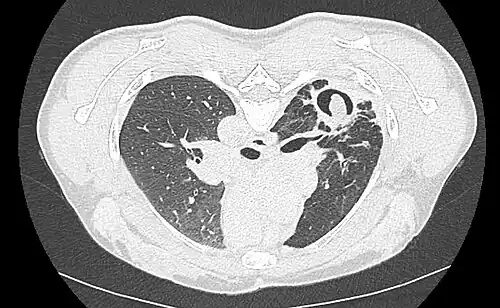

Sur la radiographie pulmonaire, un aspergillome simple apparaît comme un nodule dense, le plus souvent entouré d'un croissant aérique[11]. La radiographie seule ne suffit pas au diagnostic ; un scanner est recommandé[29]. Sur le scanner thoracique, le centre de la cavité est occupé par l'aspergillome[58]. La pseudo-tumeur bouge dans la cavité lorsque le patient change de position (signe de Monod)[58]. Dans l'aspergillome simple, il n'y a pas d'évolution entre les examens et la paroi de la cavité est le plus souvent fine[13]. Un aspergillome complexe[13] présente en revanche l'aspect d'une cavité (ou plusieurs) à parois épaisses, comportant en son centre une truffe aspergillaire. Il existe parfois un début de fibrose pulmonaire[59]. La plèvre adjacente a également un aspect fibrosé, et l'évolution radiologique est lente, mais toujours vers l'aggravation[13]. Un halo en verre dépoli peut également entourer les lésions[45].

- Aspect scannographique typique d'un aspergillome développé dans une caverne tuberculeuse.

- Le changement de position modifie la position du grelot aspergillaire dans la cavité (signe de Monod).